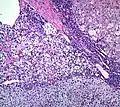

Histopathology

The microscopic histopathology analysis of the tissue samples obtained from the adrenal cortex of individuals presenting with adenoma-associated symptoms such as primary aldestronism (PA) indicates that adenoma cells are relatively larger with different cytoplasm, and increased variation in nuclear size. This indication is based on comparison between the healthy (normal) and affected (adenoma-associated) adrenal cortex tissue samples.

Adrenocortical adenoma with focal high grade nuclear atypia

Adrenocortical adenoma with focal necrosis_adrenocortical_adenoma.jpg.webp)